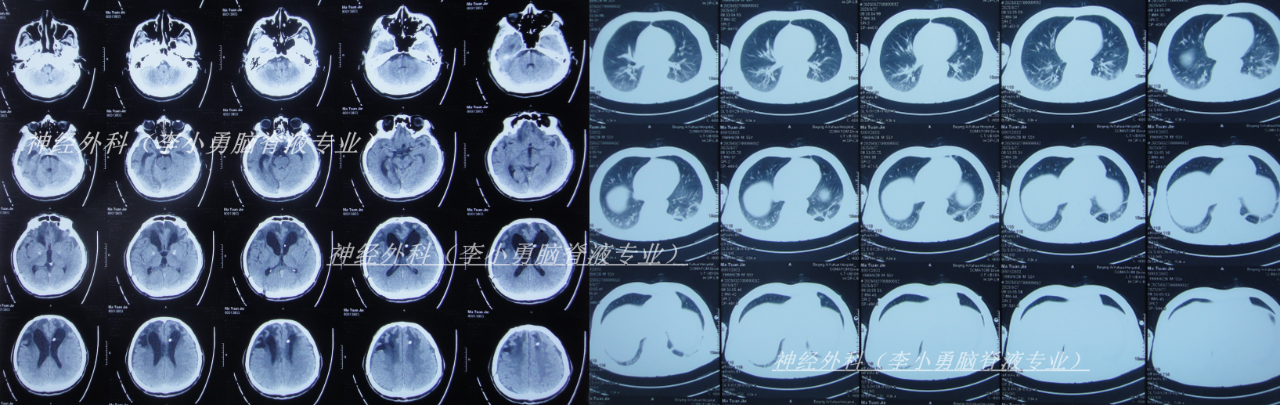

治疗4天后即2025年1月13日,仍发热,查头颅CT(图-7)和肺部CT(图-8)后继续抗感染治疗。

图-7:2025年1月13日头颅CT

图-8:2025年1月13日肺部CT

保守治疗1周没有效果,于2025年1月18日(颅骨修补术后93天即脑室腹腔分流术后121天),再次选择了北京另一所三甲医院,查头颅CT(图-9)后急诊留观,行脑脊液检查提示人类疱疹病毒。

图-9:2025年1月18日头颅CT

该院治疗10天即2025年1月27日,查头颅CT示脑室进一步扩张(图-10)。

图-10:2025年1月27日头颅CT